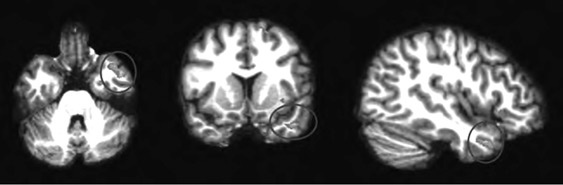

Анализируя далее научную литературу, мы пришли к выводу, что процесс поведенческого подражания с участием верхних отделов височной коры и эмоциональный (физиологический) резонанс, требующий участия островка, тоже имеют отношение к системе зеркальных нейронов. При подражании верхние отделы височной коры кодируют сложные процессы сенсорных следствий двигательных актов; при эмоциональном резонансе островок осуществляет физиологический и аффективный сдвиг, имитирующий его у другого человека. Исходя из параллелизма этих функций реципрокного действия (имитационной, физиологической и аффективной), мы можем использовать термин «резонансный контур», подразумевая, что в нем могут участвовать зеркальные нейроны, но не все компоненты этого контура двигательные, поэтому формально мы не можем назвать такой контур зеркальным. В нашем обсуждении мы примем во внимание это отличие и будем называть резонансный контур именно так, или будем прибегать к выражению «области, связанные с системой зеркальных нейронов» (рис. П.1 и П.2).

П.2

Иллюстрация к книге — Внимательный мозг. Научный взгляд на медитацию [i_015.jpg]

Рис. П.1, П.2. Функциональная МРТ, выполненная во время выполнения медитации осознавания дыхания. На снимках видна активация верхней височной извилины (рис. П.1) и активация островка и вентрального отдела передней поясной извилины (рис. П.2). Верхняя височная кора, островок и области срединной префронтальной коры (показанные здесь) вместе с системой зеркальных нейронов, как предполагается в тексте, содержат элементы «резонансного контура», которые активируются в ходе внимательного осознавания (снимки напечатаны с разрешения Сары Лазар © 2005)